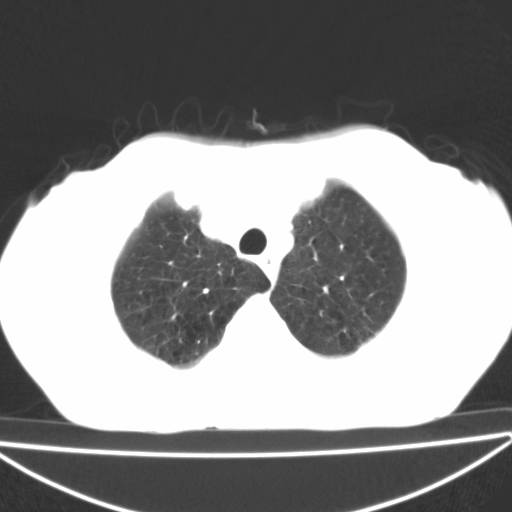

以下是引用zjzjr在2006-12-6 19:04:00的发言:[br]左肺上叶尖后段可见椭圆形高密度影,其内可见点状钙化影,周围可见卫星病灶.首先考虑结核,双侧少量胸腔积液.

以下是引用李世军在2006-12-6 19:54:00的发言:[br]左肺上叶尖后段可见椭圆形高密度影,其内可见点状钙化影,周围可见卫星病灶.首先考虑结核,双侧少量胸腔积液. [br] [br] 双肺轻度肺气肿,左肺上叶后段见多发斑片状密度增高影,周围见少许斑点状卫星病灶,双侧胸膜增厚粘连,纵隔内未见明显改变,考虑结核可能性大,请结合临床或增强扫描. [br] [br]

以下是引用13081830109在2006-12-6 19:35:00的发言:[br]左肺上叶尖后段可见椭圆形高密度影,其内可见点状钙化影,周围可见卫星病灶.首先考虑结核,双侧少量胸腔积液.

以下是引用守望可可西里在2006-12-7 0:01:00的发言:[br][quote]以下是引用zjzjr在2006-12-6 19:04:00的发言:[br]左肺上叶尖后段可见椭圆形高密度影,其内可见点状钙化影,周围可见卫星病灶.首先考虑结核,双侧少量胸腔积液.